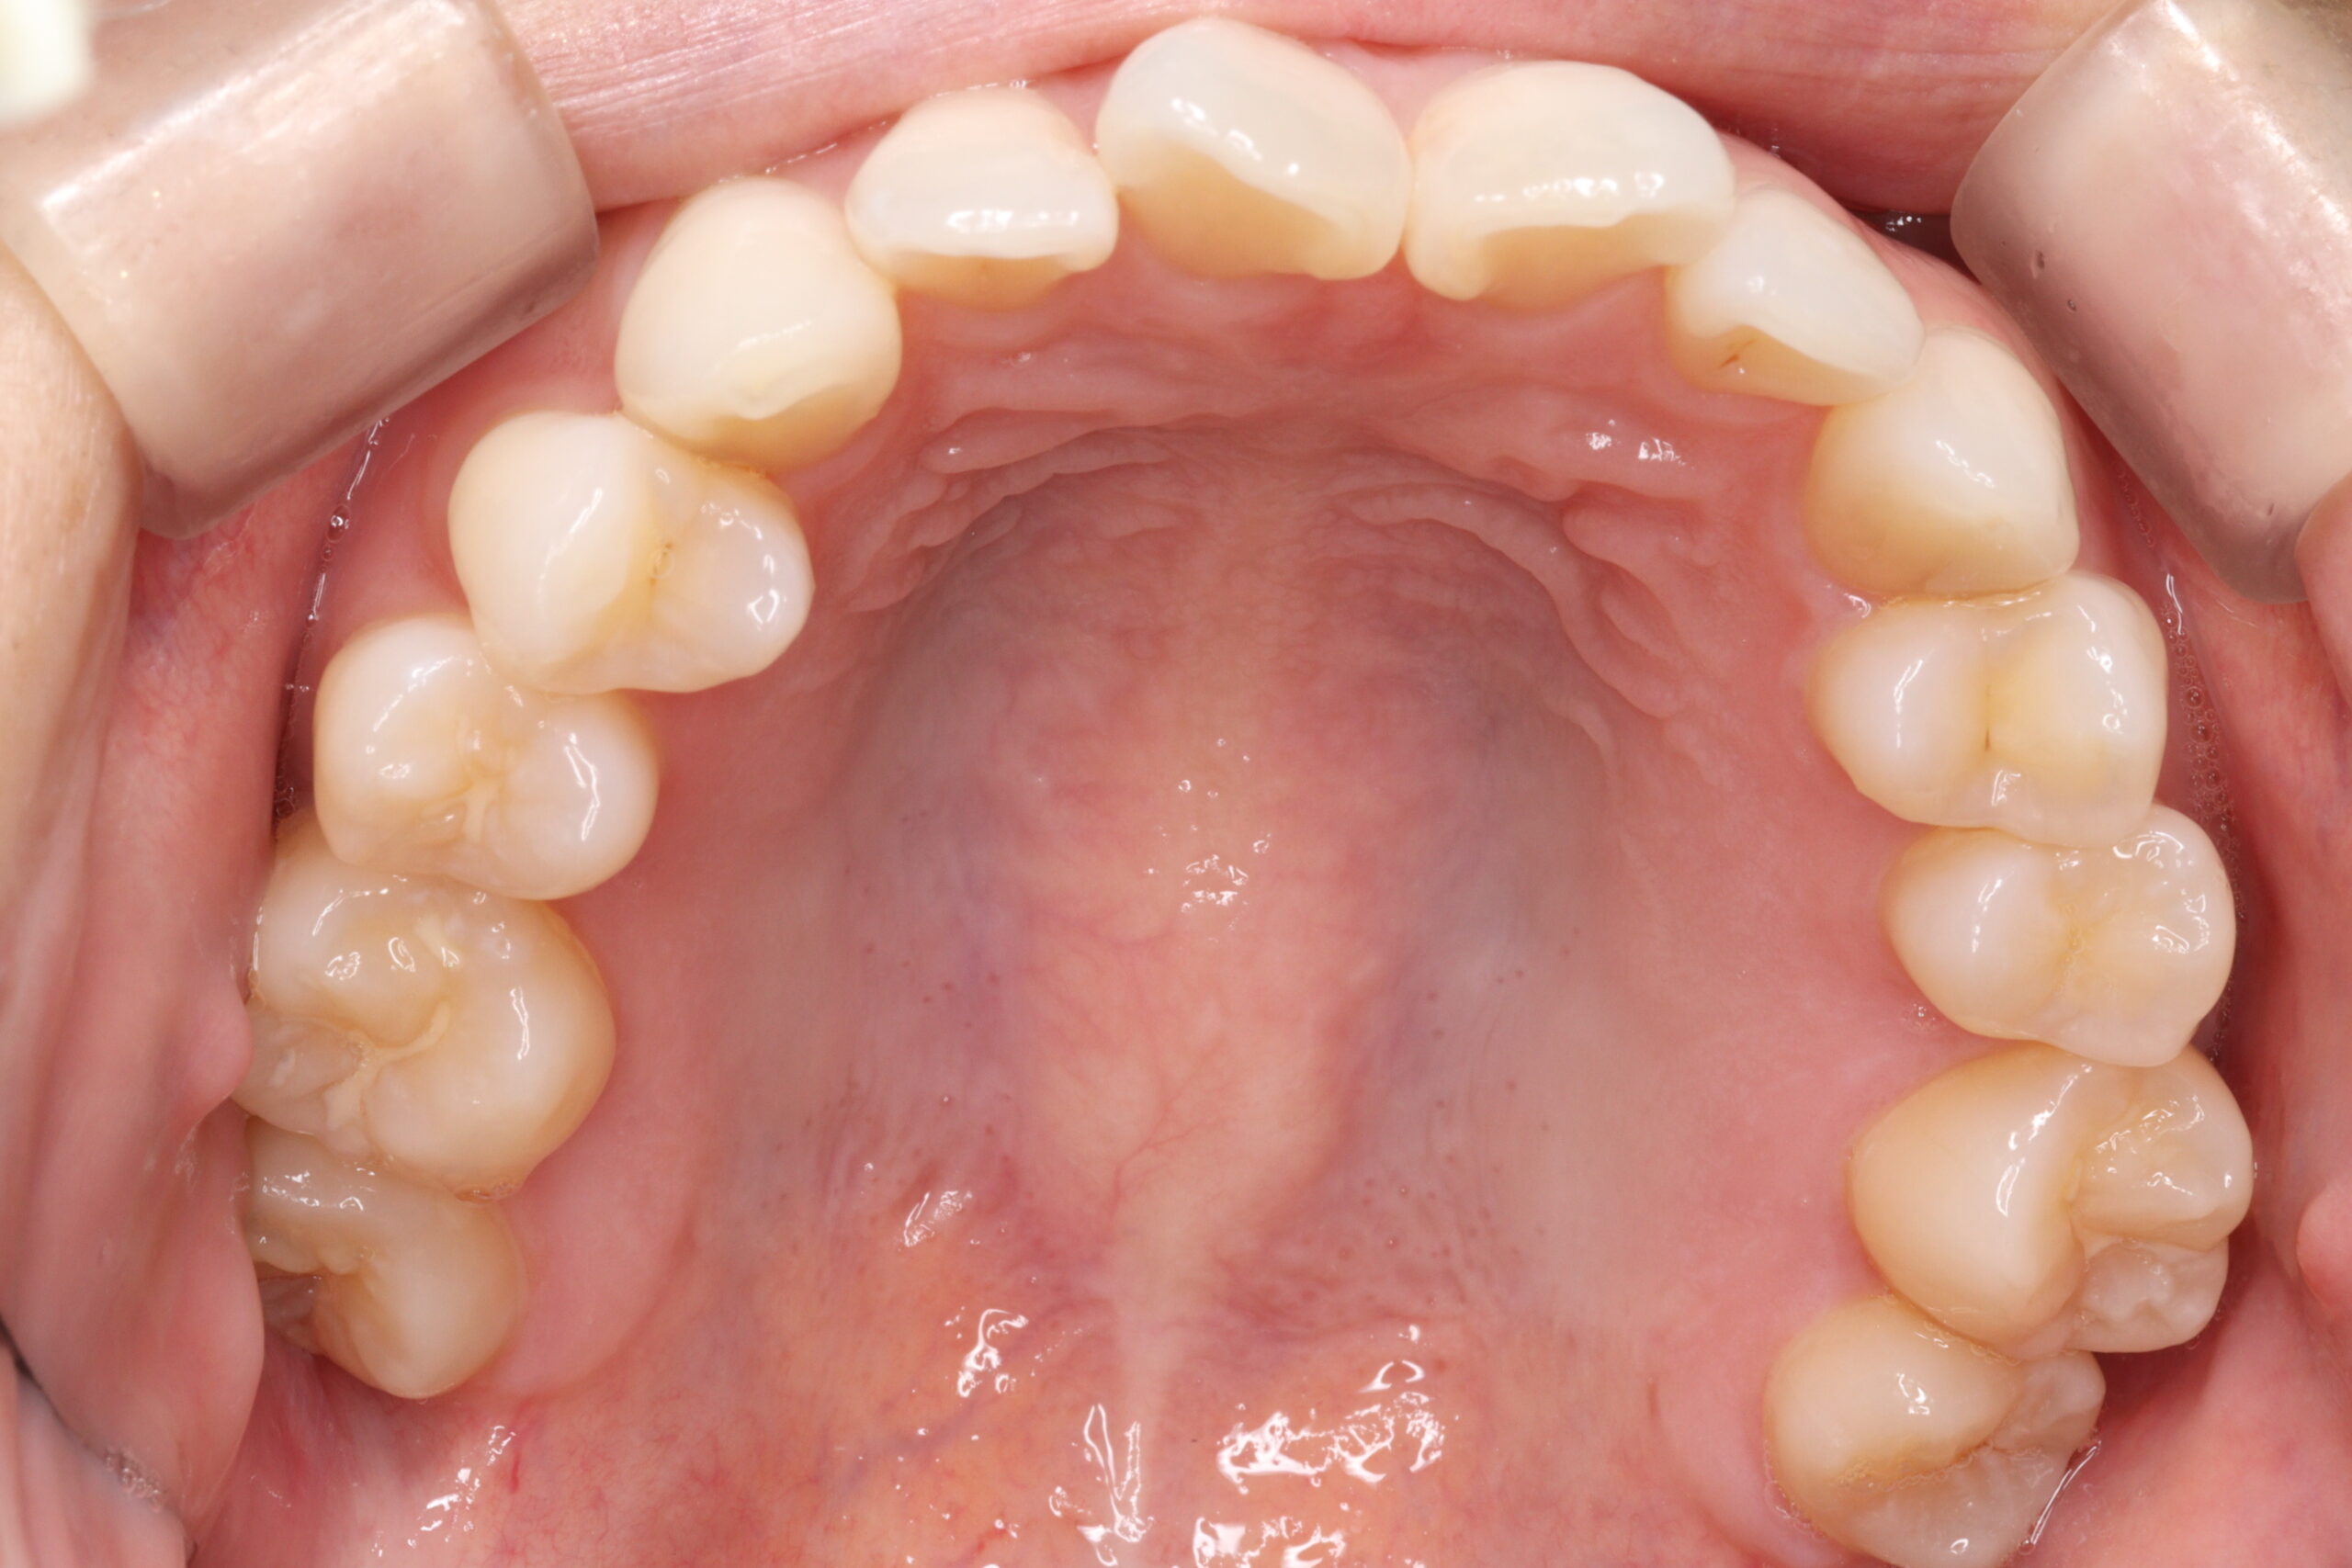

矯正術前:上顎

矯正術後:上顎